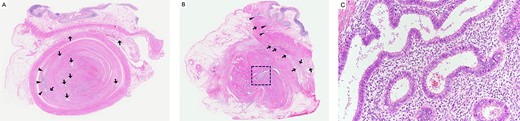

A 37-year-old woman presented with an acute onset of diffuse abdominal pain and vomiting unrelated to menstruation. The patient had no history of abdominal surgery, including a caesarean section. Her faecal occult blood test results were positive for the last 3 years, and the annual colonoscopy did not reveal any abnormalities. She had ileus of unknown cause and had undergone conservative medical management at another hospital 1 year prior. Physical examination revealed abdominal distention and peritoneal irritation. Blood examination revealed a slightly elevated circulating white blood cell count of 10 020/μl, but other laboratory data were within the normal range. Computed tomography (CT) revealed ascites and a small bowel obstruction at the level of the distal ileum (Fig. 1). Her abdominal symptoms worsened quickly during the period in which these tests were performed, and she presented with panperitonitis. Therefore, immediate surgical intervention was planned. Intraoperatively, a stricture in the distal ileum, ~5-cm oral from the Bauchin valve, was observed with haemorrhagic ascites. A mass lesion was observed at the tip of the appendix, infiltrating the terminal ileum (Fig. 2). Abnormal findings, such as twitching or pigmentation, were not observed in the serosa at the same site. We performed ileocecal resection with lymph node dissection during complete mesocolic excision, considering a malignant tumour of the intestine. Macroscopically, the resected specimen showed swelling of the appendix, thickening of the intestinal wall and stenosis of the ileum (Fig. 3A and B). Histopathological examination showed fibrous wall thickening and luminal stenosis/obstruction of the appendix by marked fibrosis. Ectopic endometrial glands and stroma were scattered in the thickened appendiceal wall. Fibrous adhesion of the ileum with the appendix was seen, and ectopic endometrial tissues were also scattered in the subserosa and muscularis propria of the ileum at the adhesion site (Fig. 4A–C). These findings were compatible with appendiceal and ileal endometriosis. Sampled lymph nodes did not show findings of endometriosis. The patient was discharged on post-operative day 12 and had an uneventful course without postsurgical hormonal therapy or recurrence of endometriosis.

Histopathological findings; (A) the appendix shows wall thickening and luminal stenosis by marked fibrosis; the mucosal layer is compressed and remains at the periphery of this cross section (arrowheads); ectopic endometrial glands scatter in the appendiceal wall and submucosa of the ileum (arrow); haematoxylin and eosin (H&E) stain, ×20; (B) the lumen and mucosa of the appendix are totally absent in this cross section; a large cluster of ectopic endometrial glands and endometrial stroma is seen in the centre of the appendix (square); ectopic endometrial glands are also seen in the muscularis propria (arrowheads) and subserosa (arrow) of the ileum; H&E stain, ×20; (C) a higher magnification image of the square area in (B) shows ectopic endometrial glands surrounded by endometrial stroma; H&E stain, ×200.